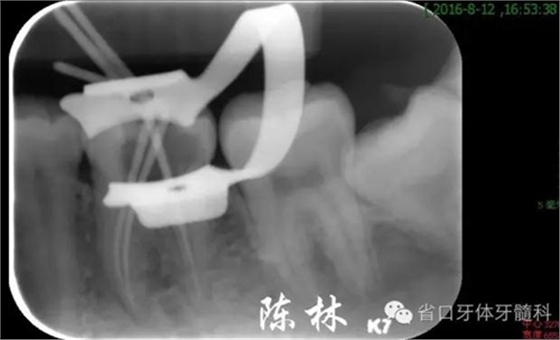

(圖6)試尖片